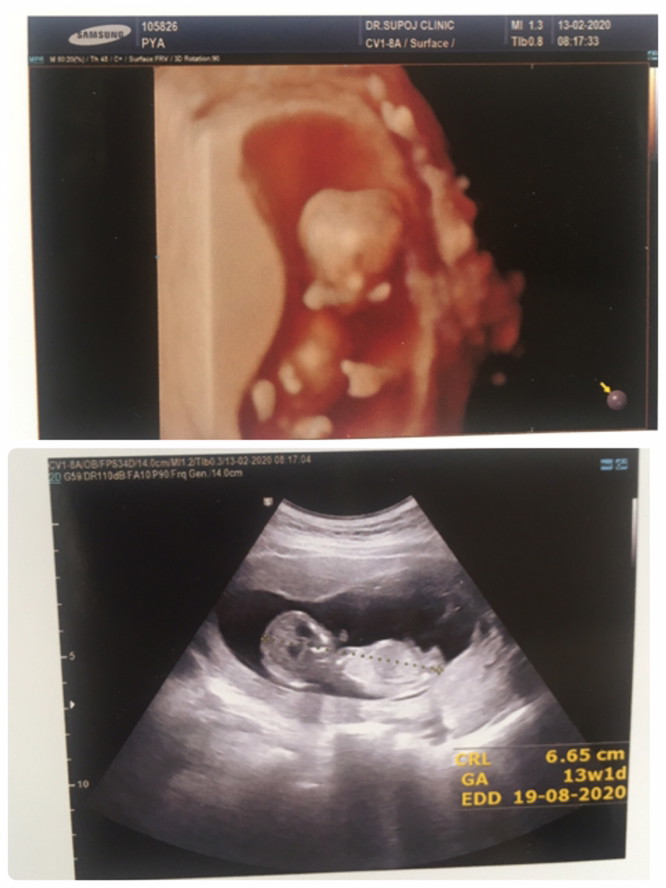

แม่ๆคนไหนมีภาพอัลตร้าซาวด์ประมาณ13วีคบ้างคะ ของเรา13วีค ภาพแบบนี้ค่ะ ดูไม่ออกเลย?

ในภาพ 13w5dคะ แต่น้องตัวโต